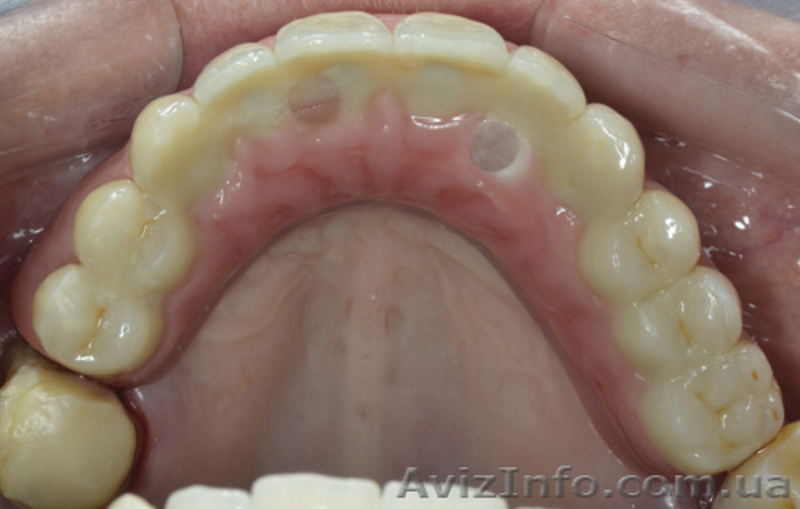

Благодаря навигационной швейцарской программе SMOP для правильного позиционирования имплантатов в нашей клинике изготавливают хирургический шаблон, который во время операции фиксируется на беззубую челюсть и по нему точно устанавливаются имплантаты. Вся операция осуществляется без разрезов, что значительно уменьшает негативные ощущения в послеоперационный период.

Также до проведения имплантации с помощью компьютерных технологий изготавливают индивидуальные абатменты (промежуточная часть между имплантатом и коронкой) из циркония, которые облегчают достижение высокого эстетического результата. Сразу после операции фиксируются индивидуальные абатменты и пластмассовые провизорные реставрации (временные коронки).

Таким образом, благодаря современным компьютерным технологиям мы имеем следующие приимущества во время имплантации при полной потере зубов: установливаются имплантаты с минимальным хирургическим вмешательством и в это же посещение фиксируется заранее изготовленная ортопедическая конструкция.